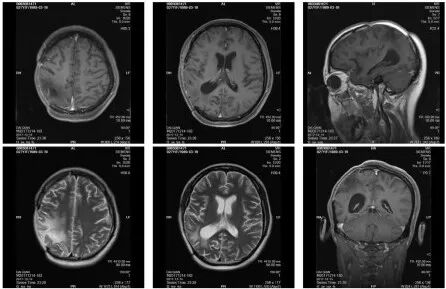

图5. 第二次术后MRI(2017.3.30)

图7. 第二次术后2个月复查MRI(2017.5.27)